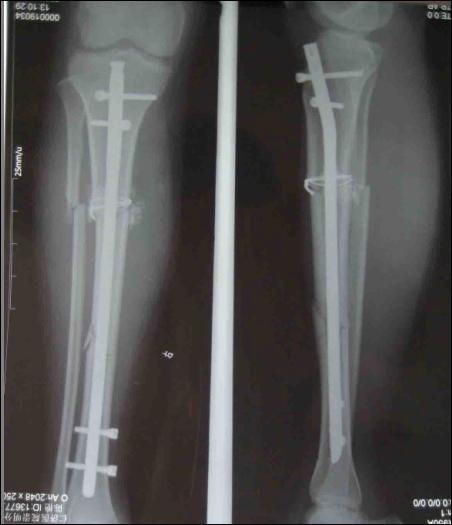

孩子脛骨骨折為何被打入鈦釘

被打入鋼釘的示意圖